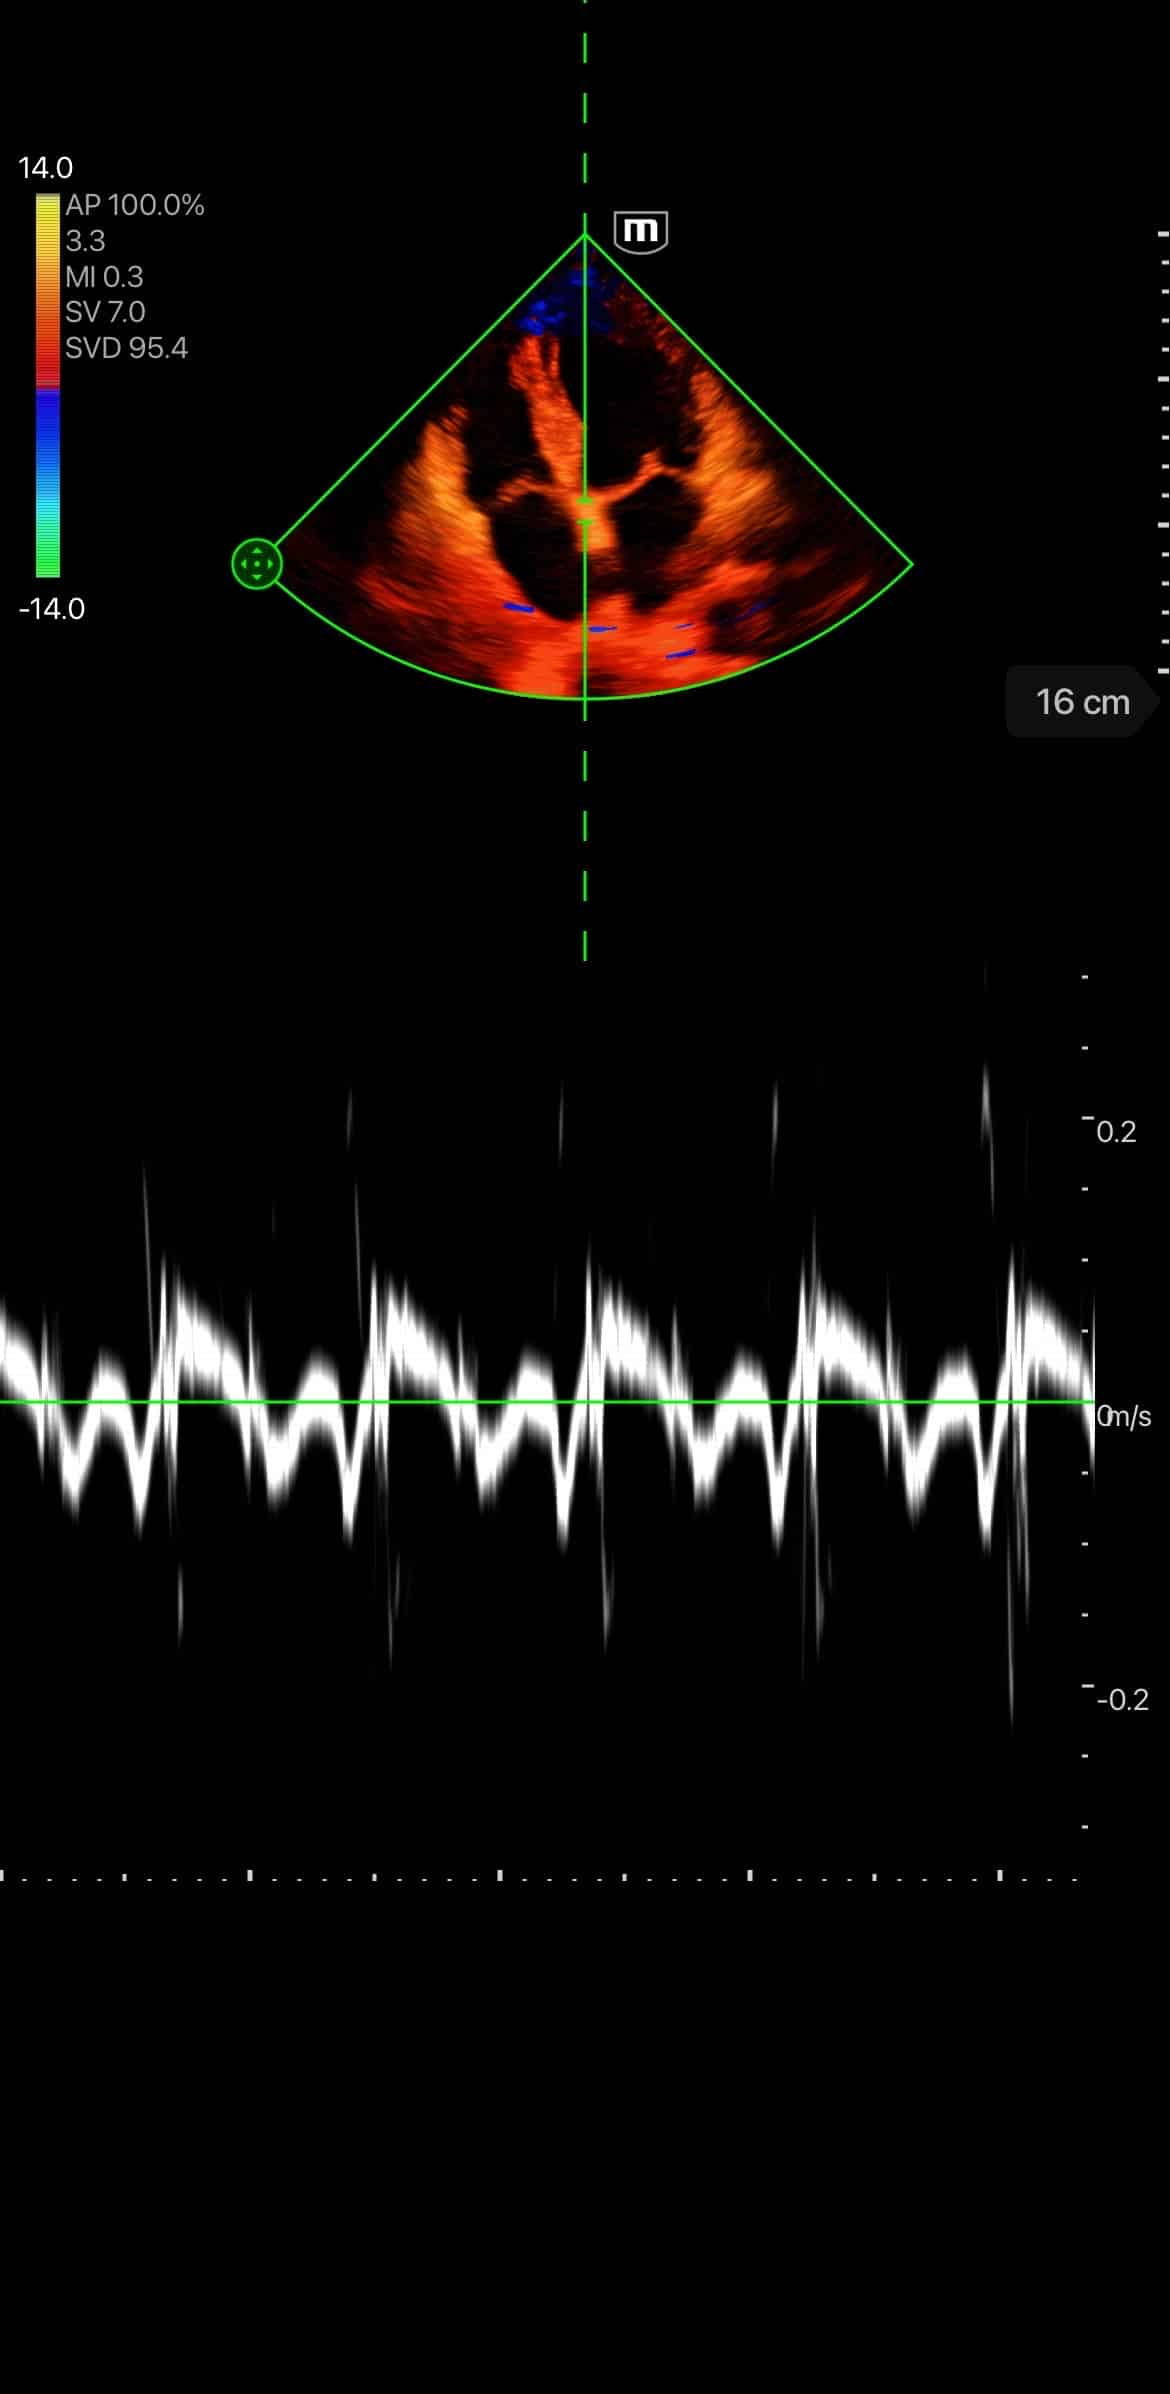

- Scanning modes: B-mode, M-mode, Color Doppler, Power Doppler, PW, and Tissue Doppler Imaging

Clinical Images